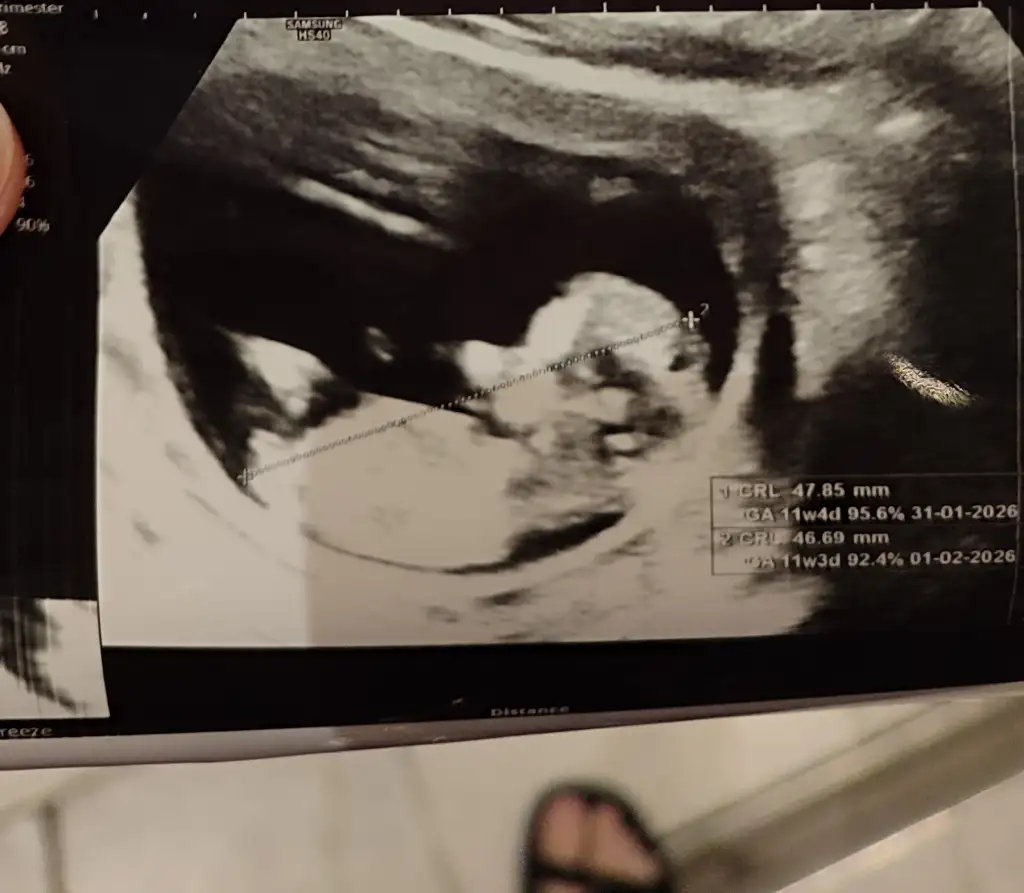

Benim bebek 1 hafta önde çıktı. 9 hafta olması gerekirken 10 hafta gözüküyor.Teyzoşlar cinsiyet tahmini alabilir miyiz ?🌸 Chat gbt erkek dıyo ama guvenmıyorum :D

Ayy hayırlı olsun canım 🥰 ben de basından beri erkek hissediyorum normalde kız istiyorduk ama erkege alıstırdım kendimi nedense 😄 senin ultrason görüntün nasıldı 11.haftada acaba buna benziyor muydu çıkıntı